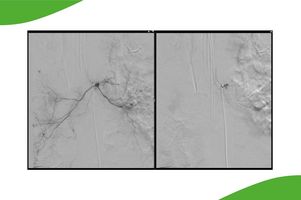

Beispiel einer Angiographie der Gesichtsarterie mit Darstellung einer komplexen Kurzschlussverbindung zwischen Arterien und Hirnvenen (sog. durale AF-Fistel).